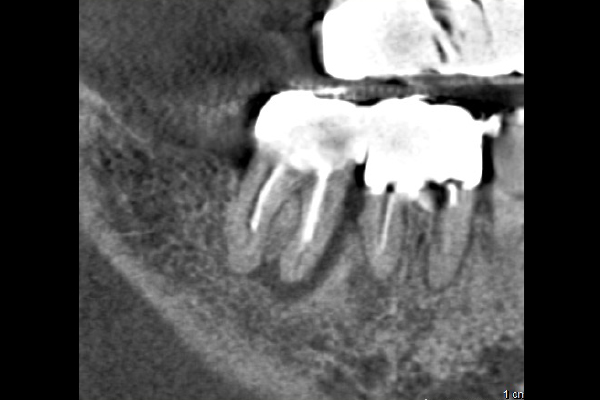

20代女性の大臼歯(奥歯)の症例

- 主訴

- 「時々歯茎が腫れる」とのことでご来院されました。数週間前から症状があり、他の医院では「抜歯の可能性がある」と言われ、不安に感じていらっしゃいました。

- 期間

- 治療期間2ヶ月、治療回数3回、レントゲン写真で治癒を確認できるまでの期間6ヶ月

- 治療内容

- 1.古い被せ物の除去と虫歯の徹底除去

まず、古い銀歯を外し、内部に広がっていた虫歯を丁寧に取り除きました。

2.マイクロスコープ下での根管治療

唾液などによる細菌の侵入を防ぐ「ラバーダム」を装着し、マイクロスコープ(歯科用顕微鏡)で根管内を数十倍に拡大しながら治療を進めました。複雑な形状の根管の内部まで、汚染された組織を徹底的に洗浄・消毒します。

3.根管充填(こんかんじゅうてん)

根管内が完全にクリーンになったことを確認し、再感染を防ぐために専用の薬剤で隙間なく密閉しました。

4. 土台と被せ物の作製

歯の強度を補うための土台を立て、最終的なセラミックの被せ物を作製し、装着しました。

- 治療に伴うリスク

- 少しでも汚染物質が残ると再発のリスクが高まります。